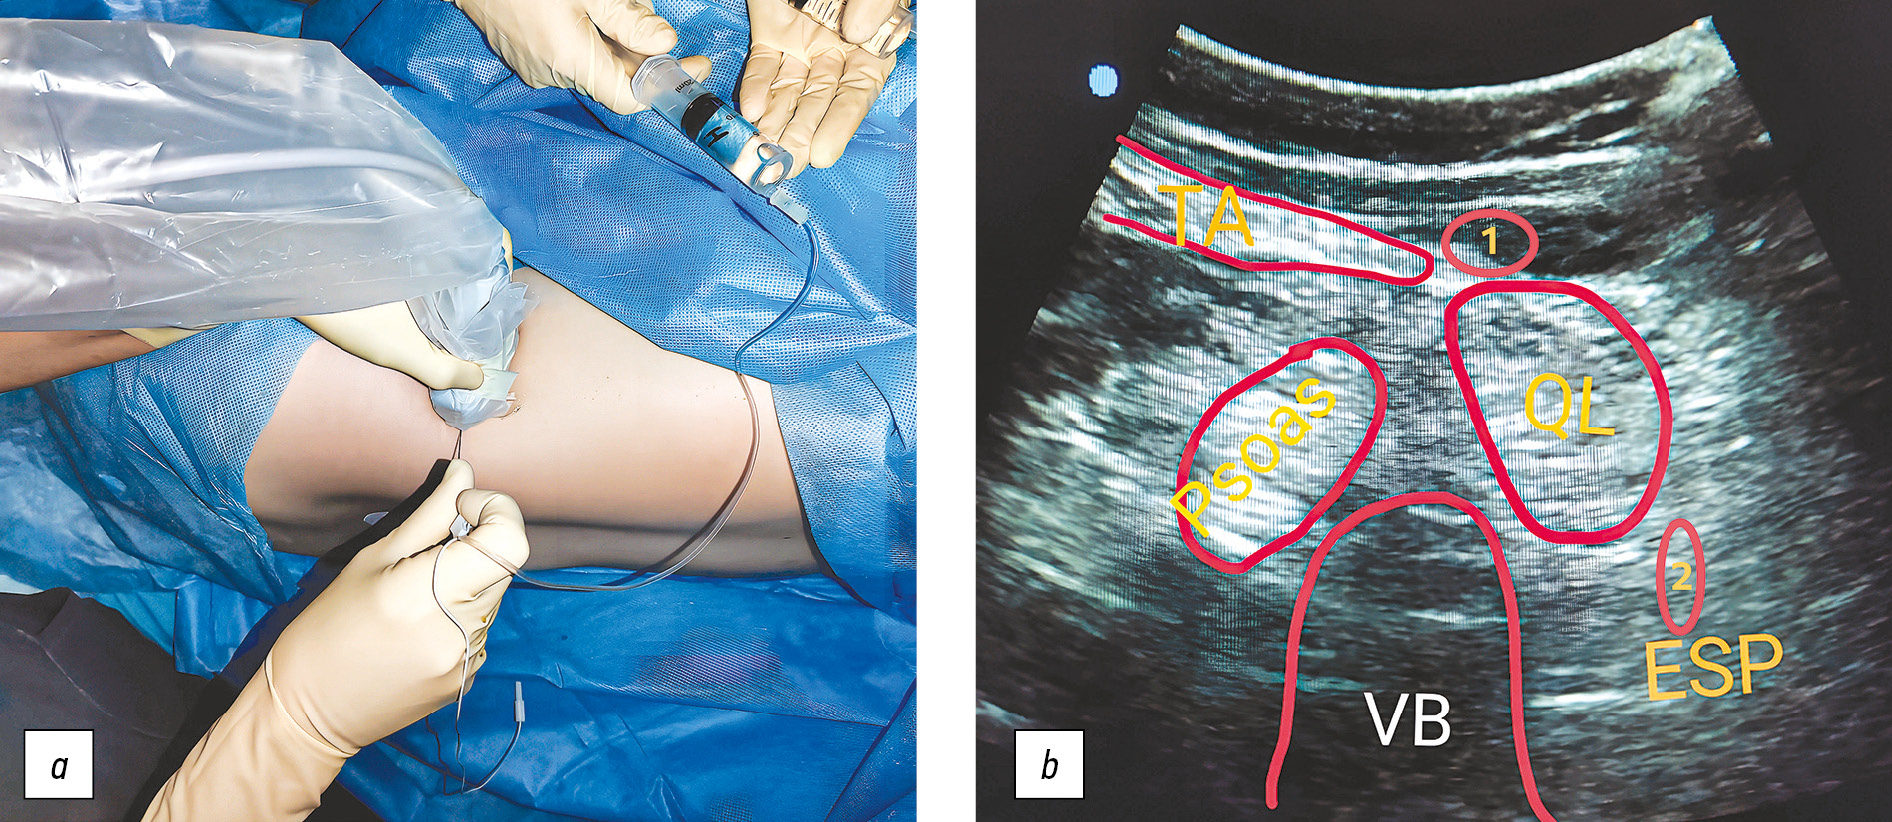

Положение пациента — лёжа на здоровом боку. После асептической обработки низкочастотный конвексный ультразвуковой датчик частотой 5–2 МГц (Sonimage FUJIFILM SonoSite SII, Япония) устанавливали по задней подмышечной линии (рис. 2, a). Идентифицировали структуры, формирующие УЗ-картину «трилистник»: поперечный отросток позвонка LIII, мышца, выпрямляющая позвоночник, большая поясничная мышца и квадратная мышца поясницы (рис. 2, b), а также мышцы передней брюшной стенки: наружную и внутреннюю косую и поперечную мышцы живота.

Рис. 2. Техника выполнения комбинированной блокады квадратной мышцы поясницы (фото из личного архива А.А. Ежевской). a — положение датчика и иглы на теле пациента, b — ультразвуковое изображение квадратной мышцы поясницы и областей введения местного анестетика, VB — поперечный отросток позвонка LIII, Psoas — большая поясничная мышца, QL — квадратная мышца поясницы, ESP — мышца, выпрямляющая позвоночник, TA — поперечная мышца живота, 1 — область введения местного анестетика при БКМП-1, 2 — область введения местного анестетика при БКМП-2.

Fig. 2. The technique of performing the quadratus lumborum block (provided by the Anna A. Ezhevskaya). a — the position of ultrasound probe on the patient’s body, b — ultrasound image of QL muscle and areas of administration of the local anesthetic, VB — transverse process of vertebra LIII, Psoas — muscle psoas major, QL — quadratus lumborum muscle, ESP — erector spine muscle, TA — transverse abdominal muscle, 1 — place of administration of local anesthetic for QLB-1, 2 — Place of administration of local anesthetic for QLB-2.

Вначале выполняли БКМП-1. На уровне позвонка LIII вводили изолированную иглу «Stimuplex А120» (B. Braun, Германия) в плоскости датчика (in-plane) от его заднего края и продвигали в заднепереднем направлении, до границы поперечной мышцы живота с квадратной мышцы поясницы, позиционируя кончик иглы в фасциальном футляре последней. После отрицательной аспирационной пробы вводили половину заданного объёма 0,5% ропивакаина в количестве 15 мл.

Затем выполняли БКМП-2. Иглу подтягивали на 2/3 длины, перенаправляли более медиально, проводя до границы, с мышцей, выпрямляющей позвоночник, но без проникновения кончика иглы за пределы квадратной мышцы поясницы. После отрицательной аспирационной пробы вводили вторую половину объёма 0,5% ропивакаина (также 15 мл).